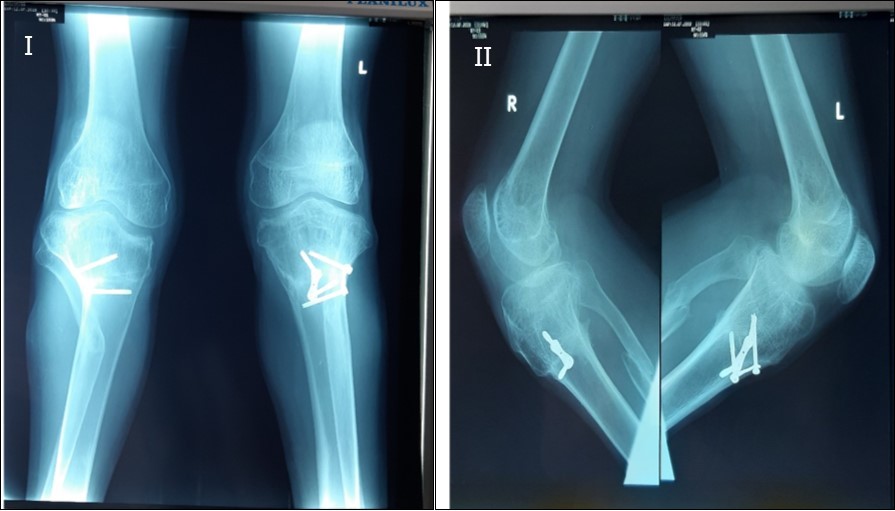

There was satisfactory correction of his deformities at his last out-patient visit, 2 years post operatively, with acceptable mobility of the knees, 0- 120 degrees of passive knee motion. Figure 7.

The patient is ambulatory and now has painless knees, a remarkable improvement in gait, no lateral knee thrust, no limb length discrepancy and is able to participate in activities at a higher level and is cosmetically optimised. Figure 8.

Figure 8.X-ray of both knees of the patient anteroposterior view, I, and lateral view II, 2yrs post operatively showing correction of the bilateral tibia vara with 8-plate and screws in situ.

X-ray of both knees of the patient anteroposterior view, I, and lateral view II, 2yrs post operatively showing correction of the bilateral tibia vara with 8-plate and screws in situ.